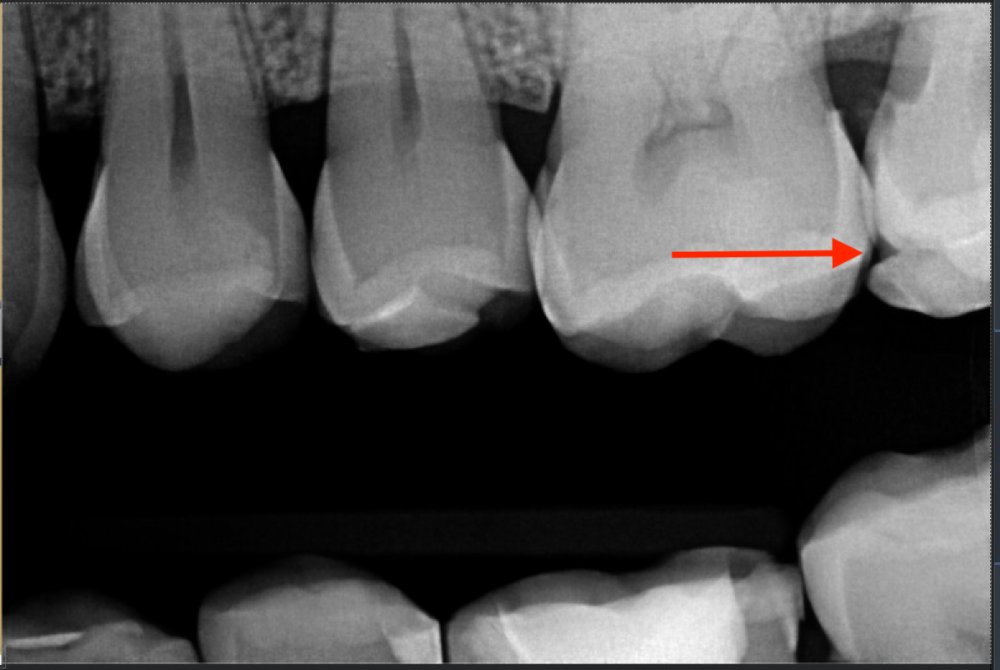

Сегодня на приеме врач заострила внимание на то что у меня откололась пломба, до этого никто мне на это не указывал( бываю у стоматологов +- раз в месяц). Зуб верхняя семерка слева. Пересмотрела старые снимки двухлетней давности, там она в таком же состоянии. Менять или не менять пломбу? Я планирую ортодонтическое лечение и ввиду высокой стоимости замены ретенционной шины хотелось бы в будущем иметь минимальное количество пломб к замене, но с другой стороны превентивно менять пломбу которая не потеряла герметичности тоже не кажется адекватным решением. Возможно ли ее доклеить?

Здравствуйте, лучше заменить. Скол создал место ретенции пищевых остатков, это рано или поздно приведет к кариесу и/или локальному пародонтиту.